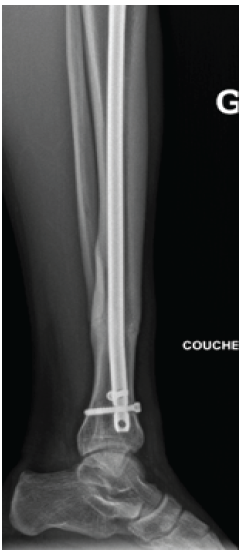

The patient followed partial weight-bearing for 4 weeks, then advanced weight bearing as tolerated. At 8 months, he was pain-free, had returned to sports, and radiographs showed maintained alignment with intact fixation (Fig. 4). Wound healing was uneventful, including at the percutaneous drilling site.

Figure 4: Follow-up lateral radiograph at 8 months postoperatively showing complete fracture union with preserved bone alignment and intact fixation following exchange nailing with the larger-diameter (10-mm) tibial nail.